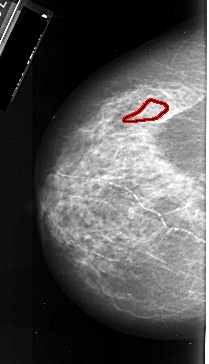

FILE: A_1019_1.LEFT_MLO.OVERLAY

TOTAL_ABNORMALITIES 1

ABNORMALITY 1

LESION_TYPE CALCIFICATION TYPE PLEOMORPHIC DISTRIBUTION LINEAR

ASSESSMENT 4

SUBTLETY 3

PATHOLOGY MALIGNANT

TOTAL_OUTLINES 1

BOUNDARY